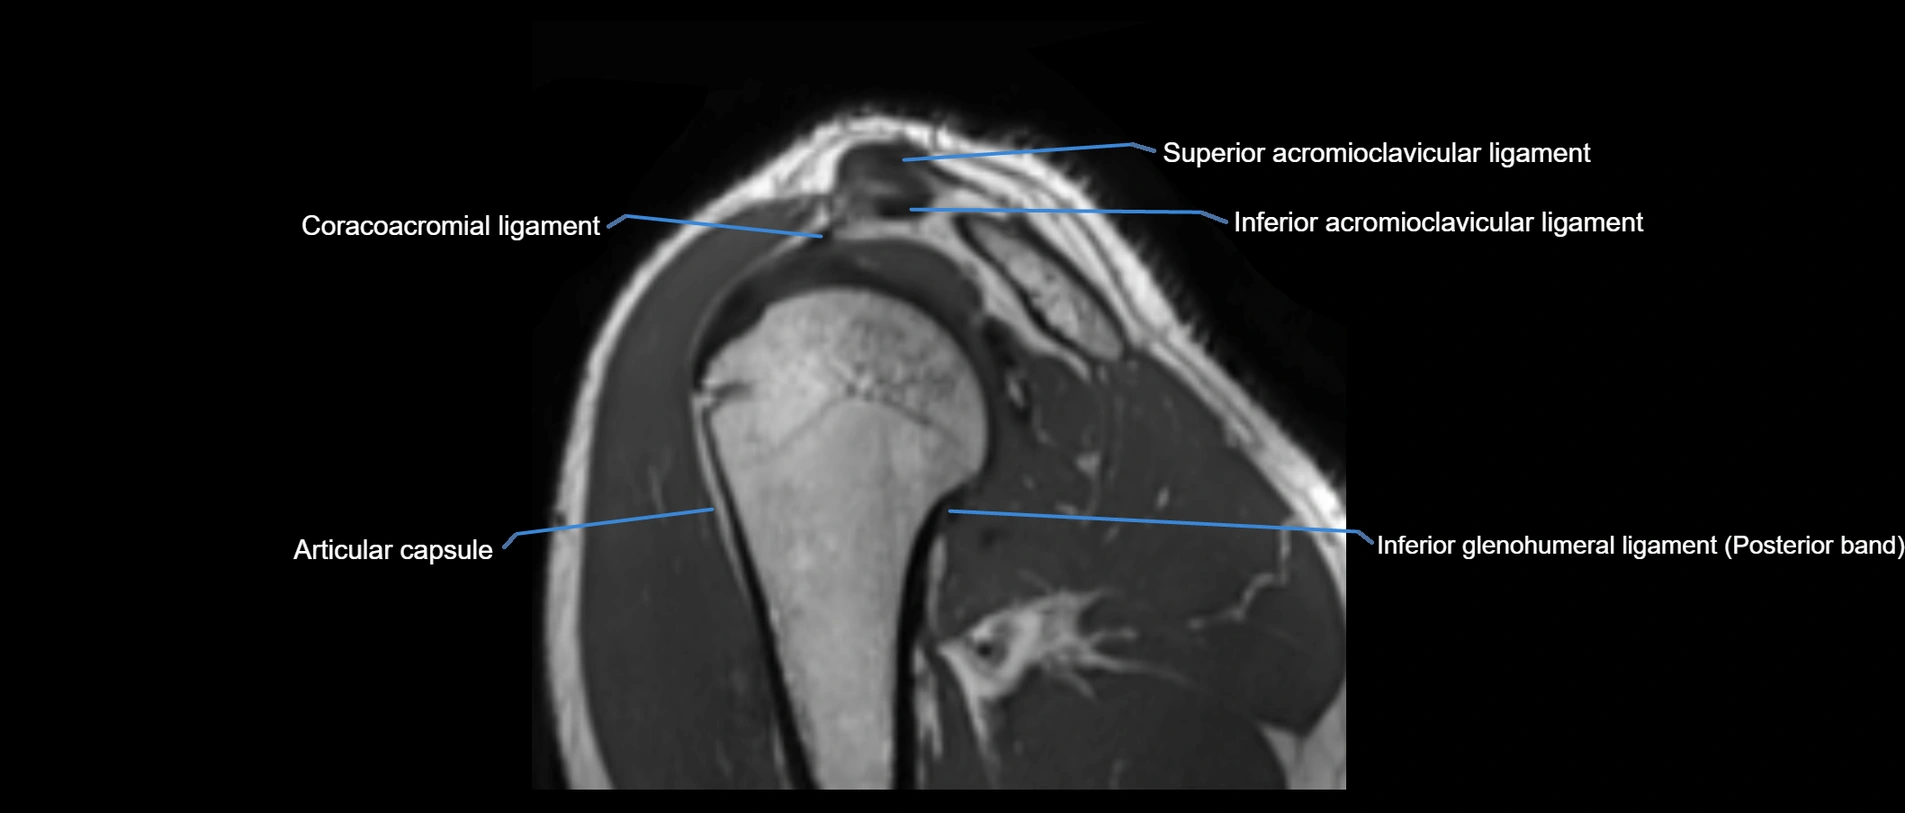

MRI Appearance

• T1-weighted images:

• Normal ligament: Low signal (dark linear band) spanning acromion to clavicle.

• Surrounding fat planes: Bright, delineating the ligament clearly.

• Marrow of clavicle and acromion: Bright due to fatty content.

• Tears: Discontinuity or irregular thickening with intermediate-to-bright signal.

• Chronic injury: Thinning, fraying, or irregular low-signal fibers with adjacent scarring.

• T2-weighted images:

• Normal ligament: Low signal, homogeneous.

• Partial tear or sprain: Focal hyperintensity or thickening.

• Complete tear: Discontinuity with fluid-bright gap between clavicle and acromion.

• Associated edema: Bright signal in distal clavicle or acromion marrow.

• STIR:

• Normal ligament: Dark linear band.

• Injury or inflammation: Bright hyperintense signal in and around ligament fibers.

• Highlights periligamentous soft-tissue edema, especially in acute trauma.

• Proton Density Fat-Saturated (PD FS):

• Normal ligament: Low signal, uniform thickness.

• Partial tear or sprain: Bright signal or contour irregularity.

• Complete tear: Clear discontinuity with bright signal gap and joint effusion.

• Excellent for assessing joint capsule, coracoclavicular ligaments, and periarticular edema.

MRI images

image